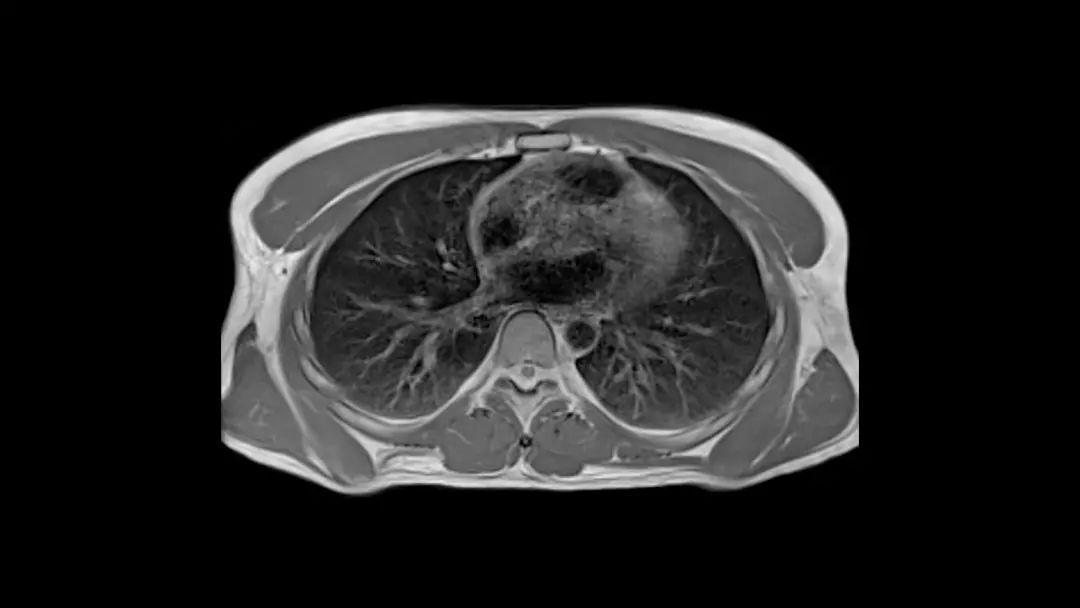

同时得益于 Deep Resolve Sharp 等基于 AI 的重建算法,0.55 T的场强提供了高诊断价值。 同时Deep Resolve 算法可执行有针对性的图像处理,可以生成和以往高场强磁共振相媲美的图像,为植入物和肺部成像等临床领域提供了优势。此外myExam Companion 等数字创新大大简化了扫描仪的操作和调整,旨在使没有经验的操作员更容易使用它。

在此前,第一台Magnetom Free.Max已经安装在德国埃朗根大学医院(Erlangen University Hospital),已有众多肺部疾病患者接受了检查。该设备携带的High-V MRI技术,可以提供了内在的物理优势,减少金属变形,从而大大提高植入物成像的诊断能力。该医院的Rafael Heiss博士表示,这款产品应用范围广泛,特别是肺部成像能力令人兴奋,同时还具有应用于新冠患者的巨大潜力。

在新冠肺炎流行期间爱尔兰根大学放射研究所,Sebastian Bickelhaupt等人使用Free.Max对新冠肺炎愈后志愿者进行了肺部随访研究,看见了以前磁共振无法看见的影像。根据得到的图像显示,Magnetom Free.Max 的肺部成像和CT具有高度的一致性。对同一志愿者Magnetom Free.Max 在不同时间的重复成像也具有很好的一致性。 在研究过程中该设备还意外的发现了部分患者的肺部结节和纤维化。